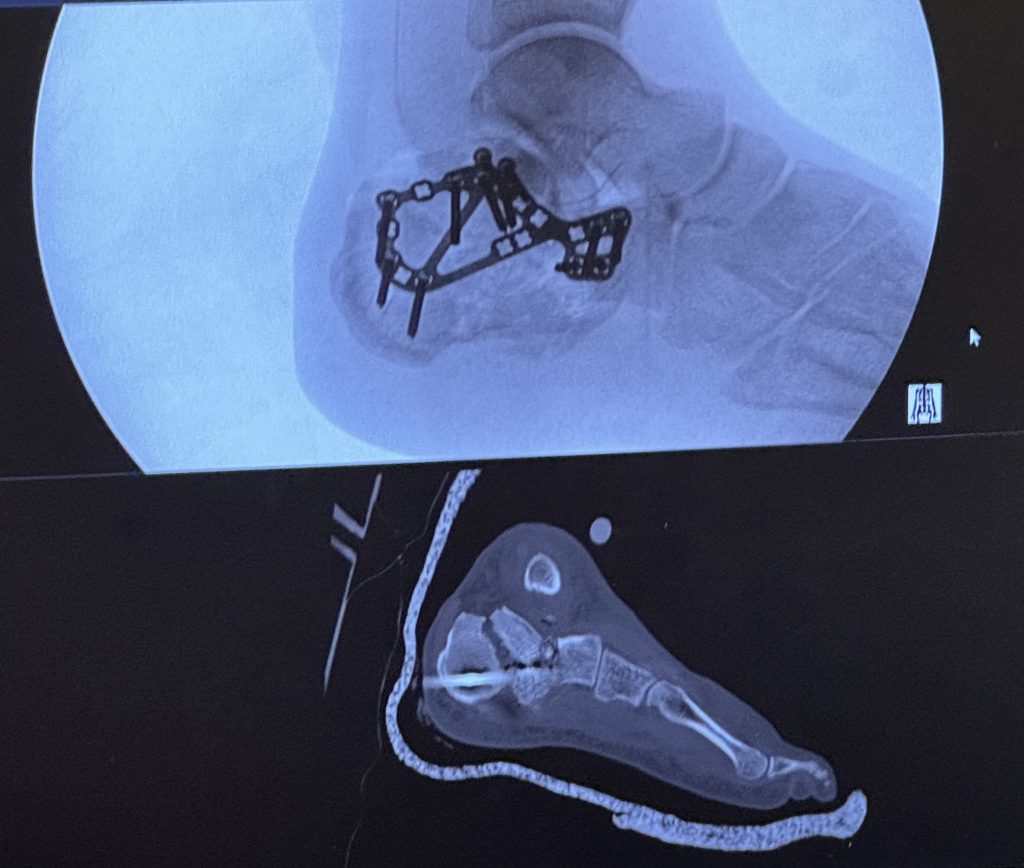

I hit a tree skiing in Colorado and suffered massive injuries to my right leg including breaking the femur, tibia, fibula and a level 6 Tibia Plateau Fracture. I was airlifted to Denver and placed in the ICU due to the extent of my injuries. After my femur was stabilized , I was flown to HSS  on a medical hospital jet and placed under the care of Dr. Helfet. Dr. Helfet, in multiple operations, rebuilt my right knee and my broken leg over the next 2 1/2 weeks. Upon my release from HSS I began physical therapy to rebuild my leg and regain my strength. 8 months after my accident I was able to ride a bicycle up the mountains on a 12.5 mile climb on a 30 mile ride.